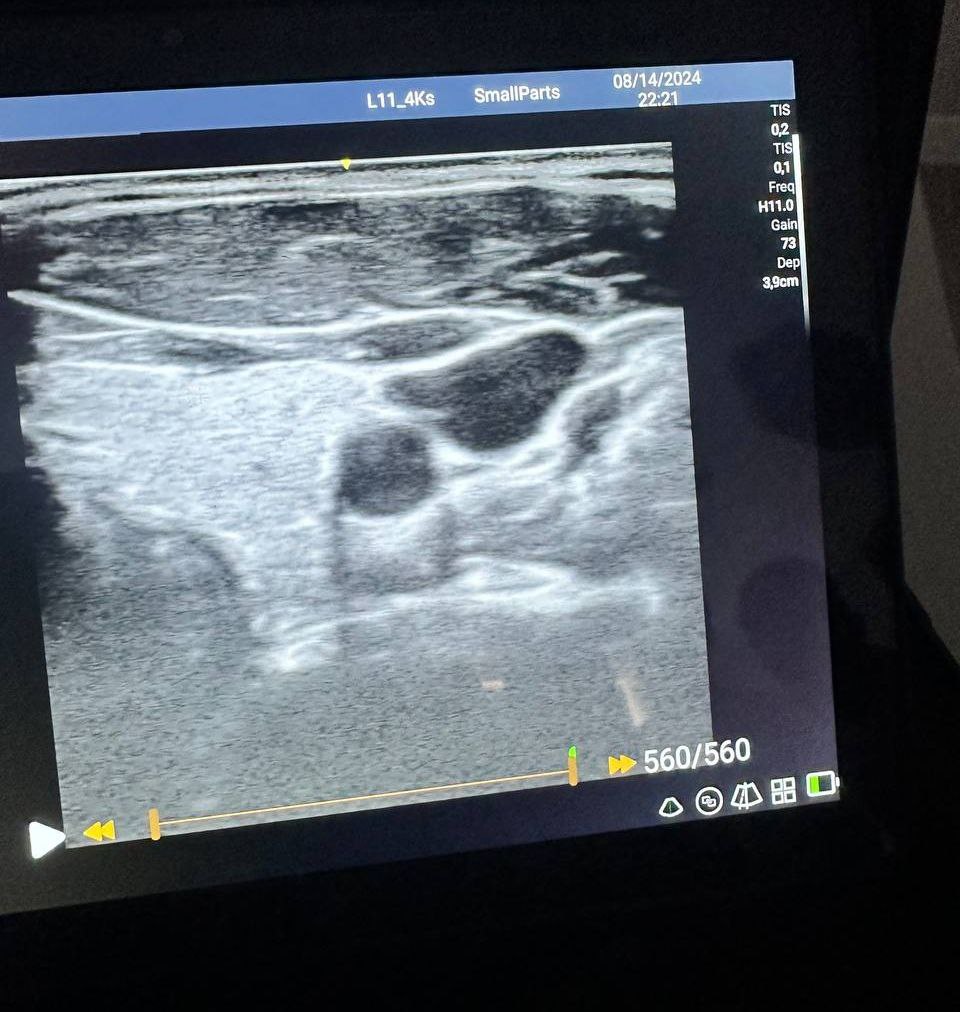

Врачи проходили обучение процедуре «медикаментозная лечебная блокада» под УЗИ-навигацией около трех дней. Пациенты замечают улучшения после первой процедуры.